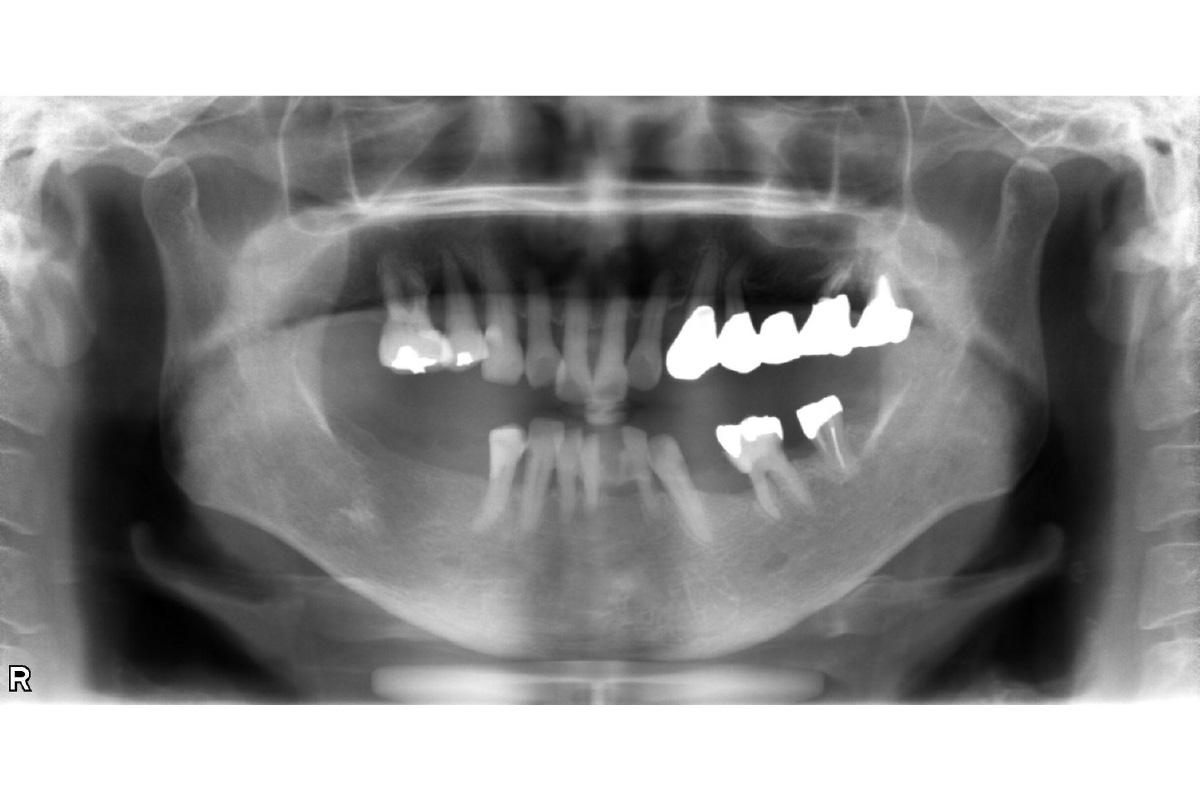

インプラント治療 オールオン4上顎の歯をキレイに治したい治療費を抑えたい 2026.03.11 上顎の歯をキレイに治したい。治療費を抑えたい。 治療前 治療後 治療前 インプラント(オールオン4) 治療後 担当医 小林 健一 先生 主訴 上顎の歯をキレイに治したい。治療費を抑えたい。 期間 費用 2,500,000円(治療時) 治療内容 仮歯 インプラント補綴(オールオン4) 静脈内鎮静法 治療に伴うリスク 外科処置を伴う 関連症例 インプラント治療審美歯科 前歯をインプラントで治したい。両隣の歯も揃えてキレイにしたい。 担当医 小林 健一 先生 主訴 前歯をインプラントで治したい。両隣の歯も揃えてキレイにしたい。 期間 4ヵ月 費用 899,800円(治療時) 治療内容 右上中切歯へのインプラント治療 (骨造成、結合組織移植) 両隣在歯のジルコニアクラウン 治療に伴うリスク 外科処置を伴う 2026-03-11 ジルコニアクラウン両隣の歯も揃えたい結合組織移植術骨造成 インプラント治療 左下の歯を入れ歯以外で治したい。前歯のブリッジはそのままで治したい。 担当医 小林 健一 先生 主訴 左下の歯を入れ歯以外で治したい。前歯のブリッジはそのままで治したい。 期間 5ヵ月 費用 566,500円(治療時) 治療内容 骨造成 結合組織移植術 インプラント治療 治療に伴うリスク 外科処置を伴う 2026-03-11 結合組織移植術骨造成 インプラント治療 下顎の入れ歯の安定が悪い。美味しい食事を取りたい。 担当医 小林 健一 先生 主訴 下顎の入れ歯の安定が悪い。美味しい食事を取りたい。 期間 5ヵ月 費用 2,457,400円(治療時) 治療内容 インプラント治療(フラップレス手術) 治療に伴うリスク 外科処置を伴う 2026-03-11 しっかり噛めるようになりたい入れ歯が合わない インプラント治療審美歯科 前歯の抜歯が必要となった。隣の歯も含めてキレイに治したい。 担当医 小林 健一 先生 主訴 前歯の抜歯が必要となった。 隣の歯も含めてキレイに治したい。 期間 6ヵ月 費用 1,179,200円(治療時) 治療内容 ジルコニアクラウン3本 インプラント治療2本 骨造成 治療に伴うリスク 外科処置を伴う 2026-03-12 ジルコニアクラウン前歯をキレイにしたい骨造成 インプラント治療 左下の奥歯を入れ歯以外で治したい 担当医 小林 健一 先生 主訴 左下の奥歯を入れ歯以外で治したい 期間 6ヵ月 費用 1,152,800円(治療時) 治療内容 抜歯・骨造成 インプラント治療 治療に伴うリスク 外科処置を伴う 2026-03-11 奥歯のインプラント骨造成 インプラント治療 前歯が折れた。抜歯はいいが、残りの歯を削らずにインプラントで治したい。 担当医 小林 健一 先生 主訴 前歯が折れた。抜歯はいいが、残りの歯を削らずにインプラントで治したい。 期間 5ヵ月 費用 686,400円(治療時) 治療内容 インプラント(抜歯即時埋入) 骨造成 カスタムアバットメント作成 治療に伴うリスク 外科処置を伴う 2026-03-11 歯が折れた骨造成 インプラント治療 抜歯となった。インプラントで治したい。 担当医 小林 健一 先生 主訴 抜歯となった。インプラントで治したい。 期間 4ヵ月 費用 455,950円(治療時) 治療内容 インプラント治療(抜歯即時埋入) 骨造成 治療に伴うリスク 外科処置を伴う 2026-03-11 抜歯即時インプラント骨造成 インプラント治療 左上の前歯が折れた。インプラントで治したい。 担当医 小林 健一 先生 主訴 左上の前歯が折れた。インプラントで治したい。 期間 4ヵ月 費用 628,650円(治療時) 治療内容 インプラント治療(抜歯即時埋入) 骨造成 結合組織移植術 治療に伴うリスク 外科処置を伴う 2026-03-23 前歯が折れた抜歯即時インプラント結合組織移植術骨造成